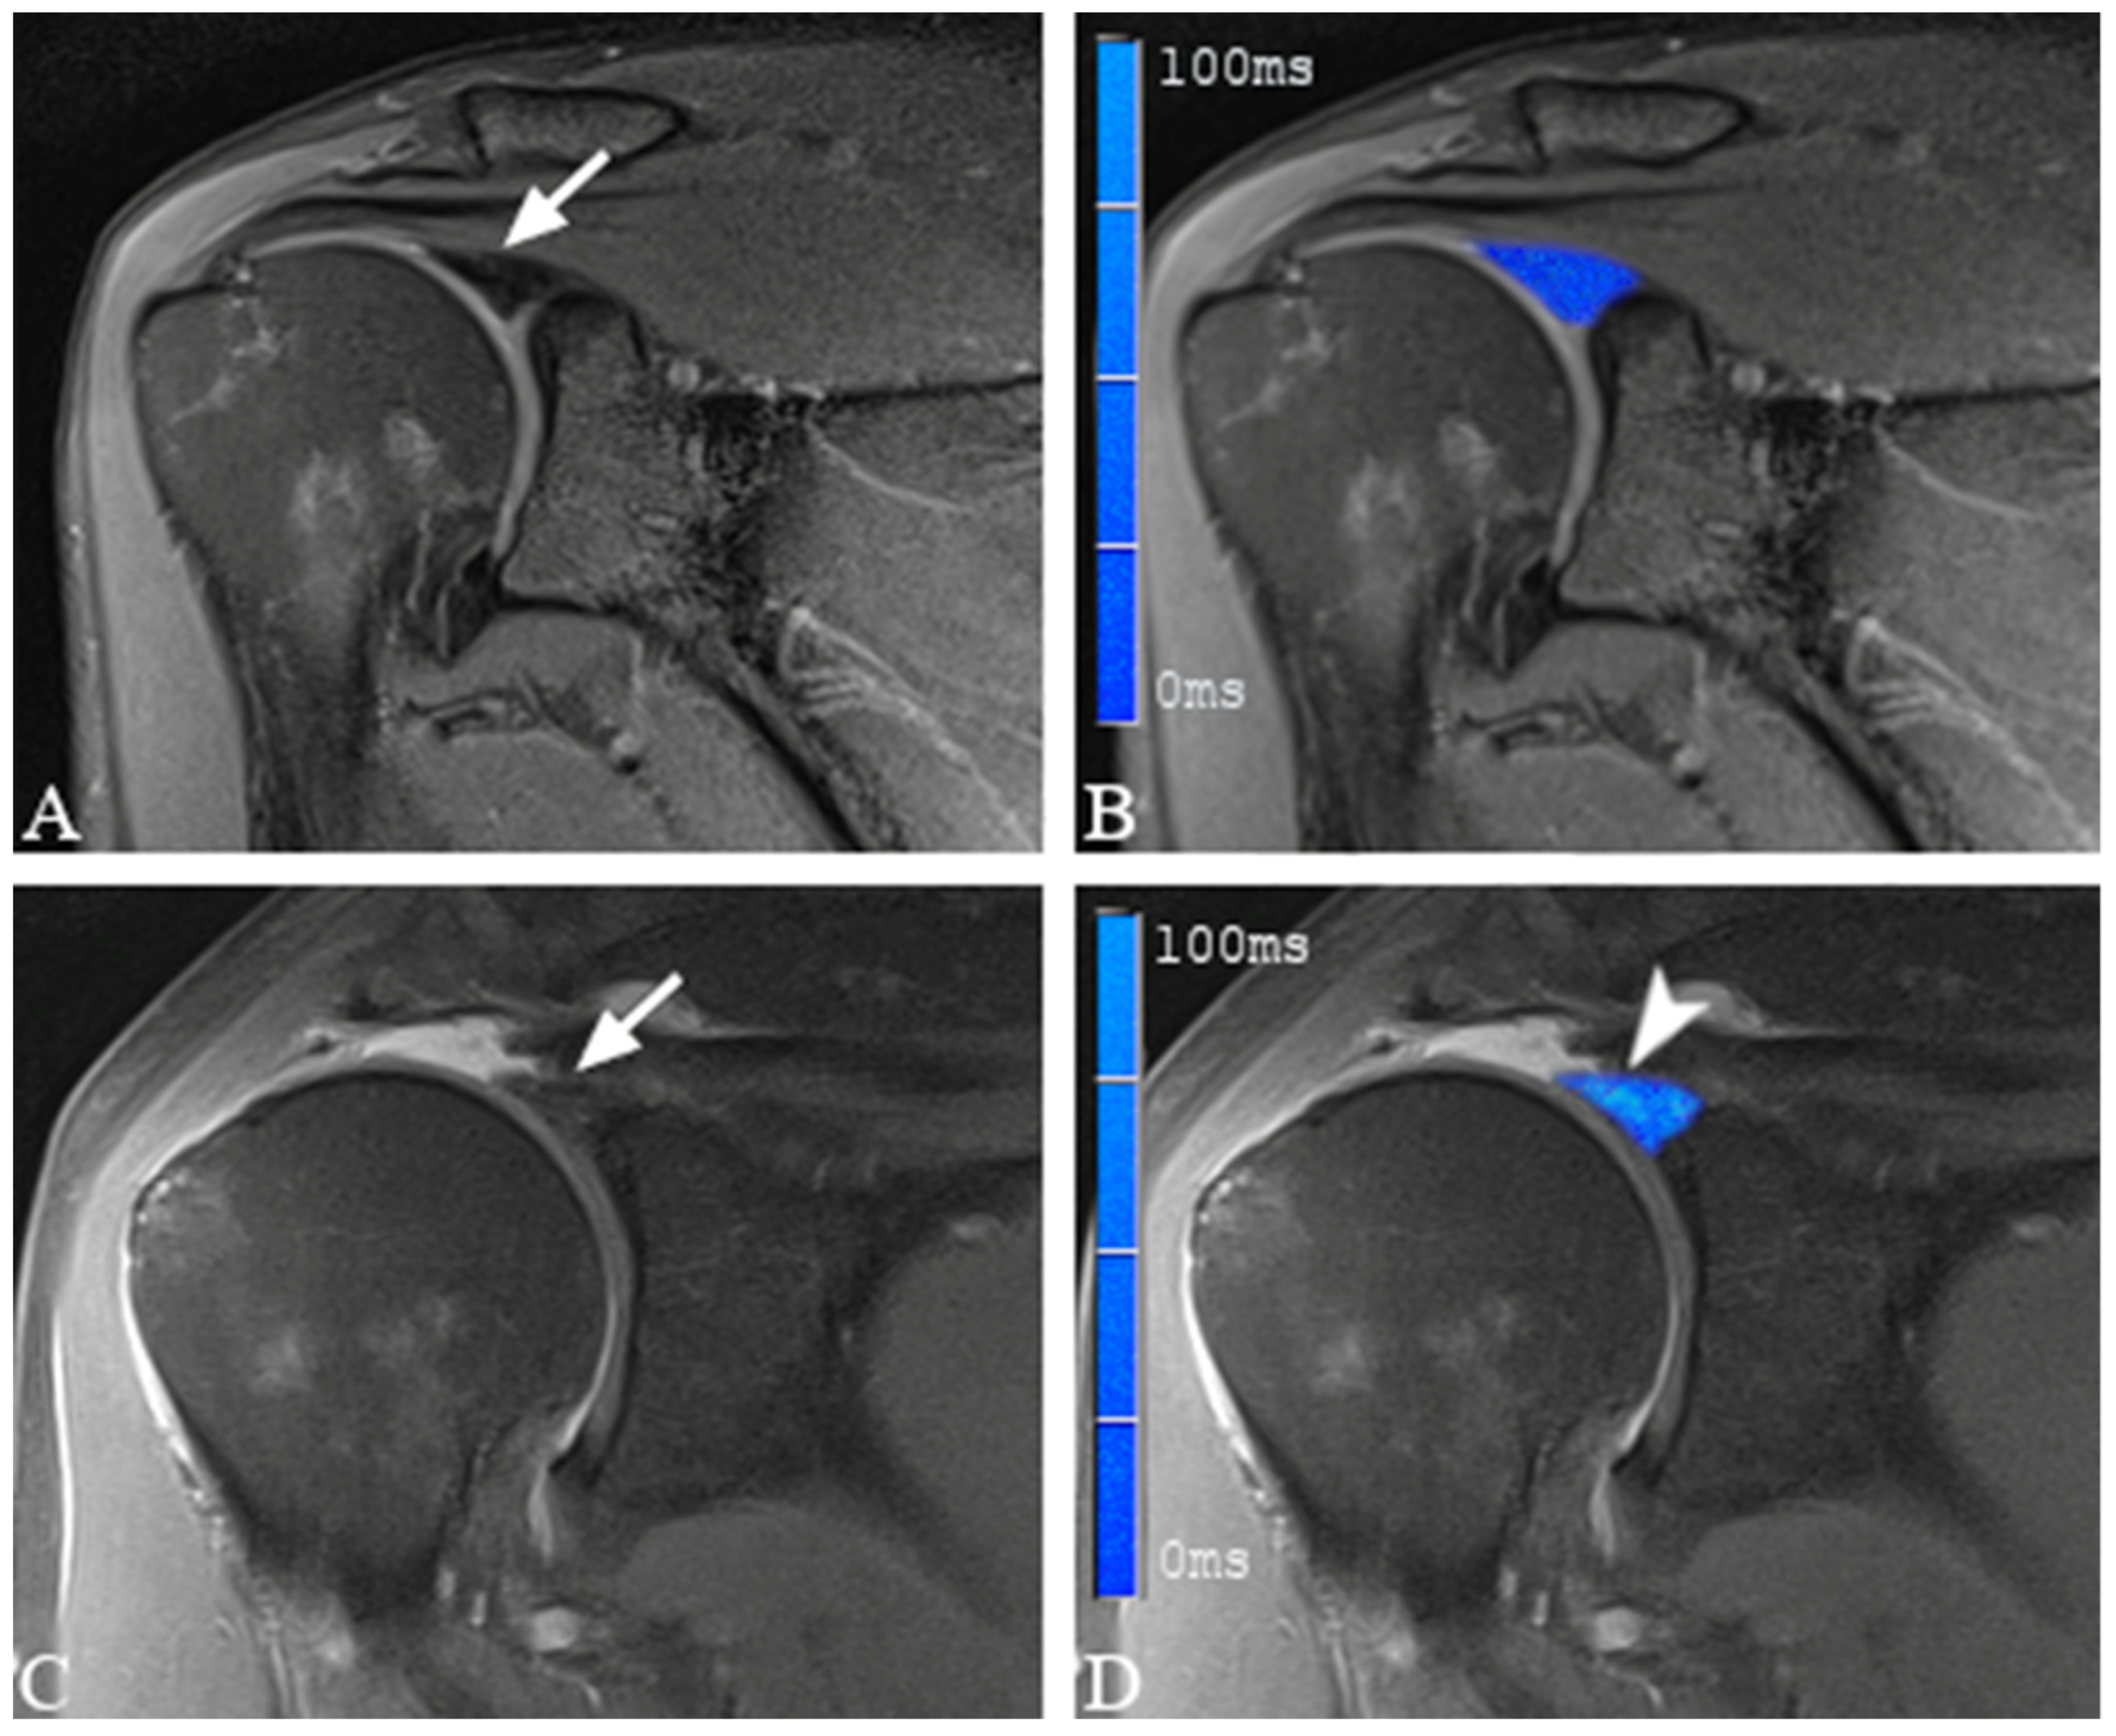

2.4. Image Analysis and Definition of SLAP Lesions

2.5. Placement of Regions of Interest